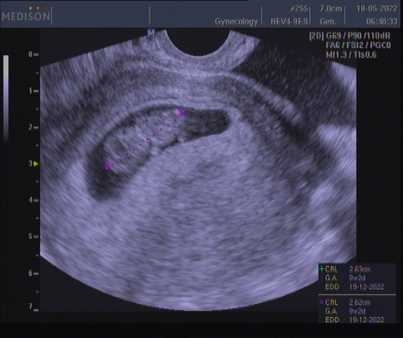

Prvni fotka 7+1 a druha 9+4 😊😊

@vero987nika prvni fotka začátek 10tt druhá fotka 4tt